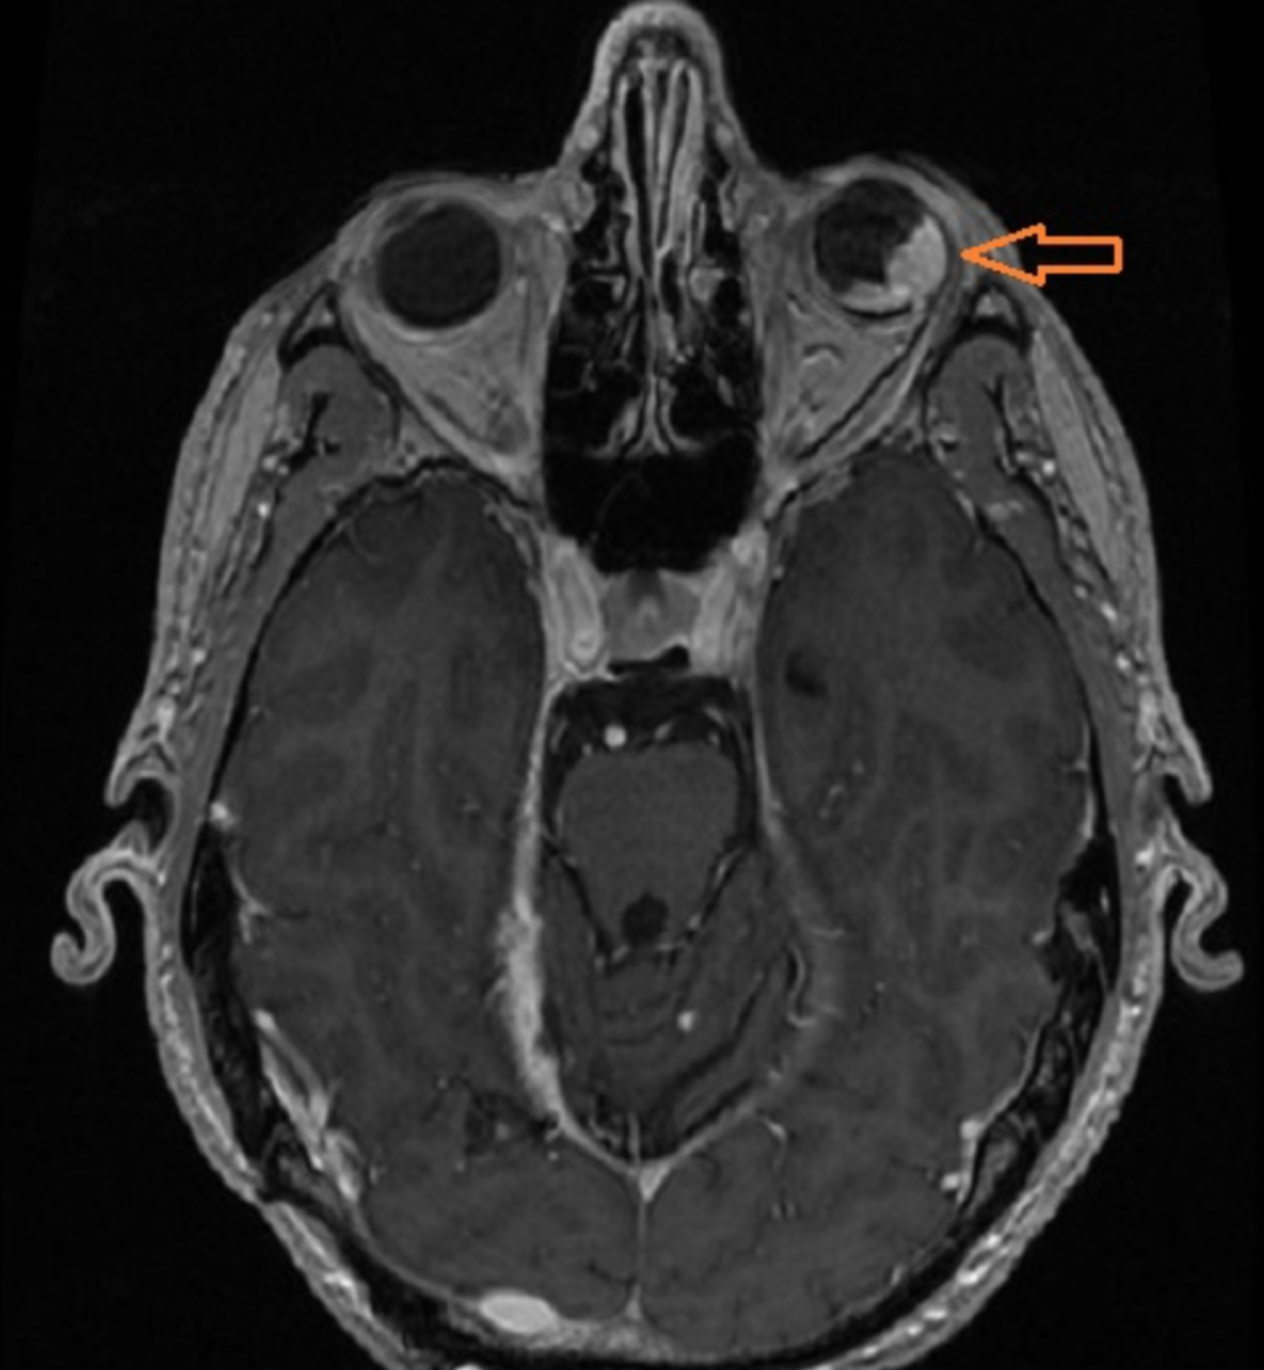

Bilateral Sturge-Weber syndrome. Postcontrast axial MR image ( A ) shows gross leptomeningeal thickening and enhancement related to the right hemisphere and less extensive abnormality of the left occipital region. Unenhanced axial T1-weighted image ( B ) shows thickening of the posterior globes bilaterally; after administration of contrast material ( C ), marked enhancement is seen in both globes. Abnormal high signal is present in this region on the proton density–weighted image ( D ). Bilateral, diffuse choroidal hemangiomas were found at ophthalmoscopy (not shown).